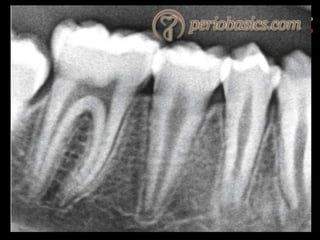

Digital subtraction radiography

 Subtraction in digital radiology is another image enhancement method with purpose

to produce two radiographs of the same area in the mouth at the different time

intervals.

 The first image can be subtracted from the second one to identify changes that may

have occurred during a certain time period. Minimal changes in loss or gain of hard

tissue can be detected using this technique, otherwise undetectable by visual

examination and traditional radiography.

77

78

digital subtraction radiography (DSR). Areas of loss and gain are represented as either

dark or light shades of grey against the neutral background.

(a) Root canal cavity is prepared.

(b) Root canal therapy is accomplished, healing is observed at the root apex.

(c) Subtraction is performed; root filling and healing zone are emphasized in light

shades of grey by DSR.

79